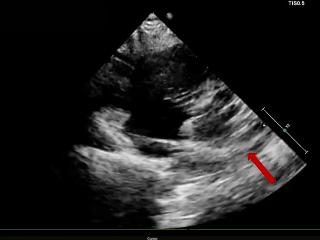

术后6个月随访

超声报告:(1)房间隔封堵器位置正常,伞盘可见部分降解,各瓣叶形态活动未见异常,右心比例稍大,左房室腔不大,心包腔内未见液性暗区; (2)多普勒检查:房水平未见残余分流;心功能:室壁运动协调,未见节段性异常;(3)先天性心脏病房间隔缺损封堵术后(可降解)未见残余分流。